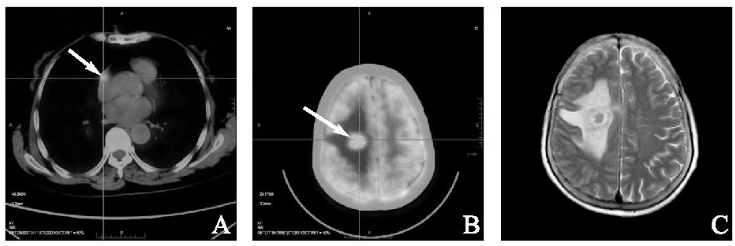

2023年2月,患者无明显诱因出现左侧肢体乏力,院外头颅CT示:右侧额顶叶占位结节伴周围明显水肿,为进一步治疗入我院。查体:左上肢、左下肢肌力4级,余肢体肌力及四肢肌张力正常。头颅MRI:右侧额叶异常信号结节,伴周围大片水肿带,结合病史考虑多系脑转移瘤或其他(图4 C)。

PET-CT示:右心房术后改变,右心房壁局部可见一稍高密度结节影,大小约1.0 cm×0.7 cm, SUVmax=6.9(图4 A),右侧半卵圆中心可见一椭圆形稍高密度结节影,大小约2.1 cm×1.6 cm, 边缘模糊,SUVmax=32.6(图4 B),其余全身未见明显转移灶。骨髓细胞学检查未见淋巴瘤浸润。经多学科会诊后综合考虑为右心房淋巴瘤术后复发累及脑组织,予以R+CHOP(利妥昔单抗600 mg d0+环磷酰胺1.1 g d1+多柔比星60 mg d1+长春新碱2 mg d1+泼尼松100 mg d1~5)方案化疗,并针对头颅病灶行全脑放疗:IMRT 95%P-GTV 40 Gy/20 Fx, 95%PTV 36 Gy/20 Fx。现患者一般情况良好,远期疗效需后期继续随访。

1736904252298270.png

图4 术后2年影像学检查。注:A:PET-CT示右房壁1.0 cm×0.7 cm高密度结节影(箭头);B:PET-CT示颅内2.1 cm×1.6 cm高密度结节影(箭头);C:头颅增强MRI示右侧额叶结节状异常信号影伴周围大片状水肿带